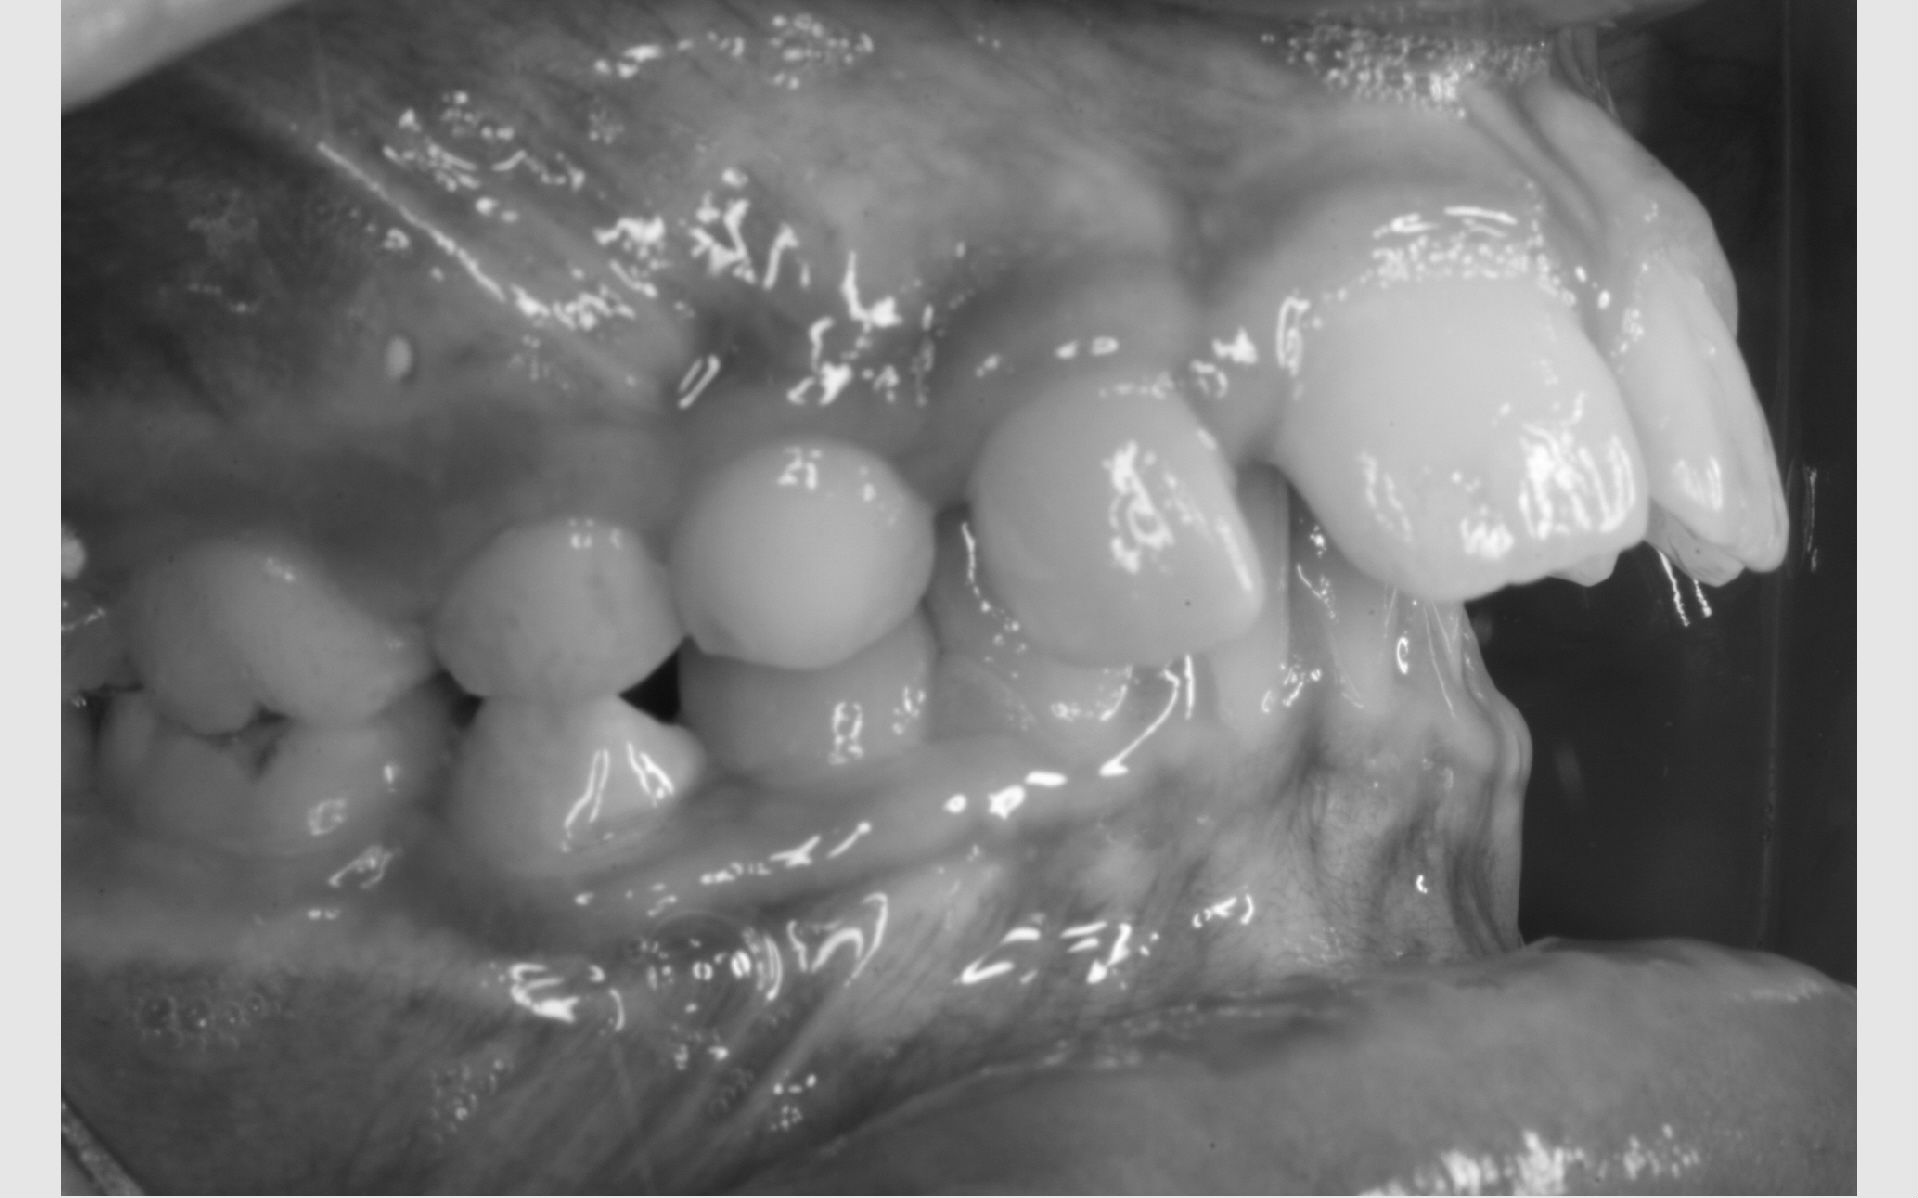

Der bliver taget billeder "udenpå og indeni" samt røntgenbilleder.

Dit barn skal selv holde sine læber til side med en læbeholder, mens tænderne bliver fotograferet. Billederne har følgende formål: